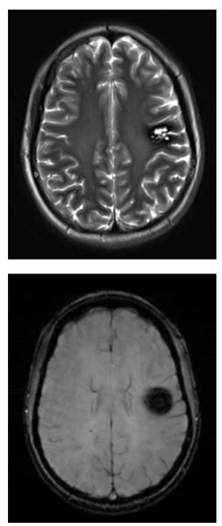

Adolescente de 16 anos realiza exame de imagem por ressonância magnética do crânio para investigação de epilepsia focal. O exame demonstra a alteração a seguir (imagem ponderada em T2 e imagem ponderada em suscetibilidade magnética (SWI), respectivamente):

Enunciado 4443569-1

(Arquivo pessoal; imagens usadas com autorização)

Considerando o exposto, é correto afirmar que o achado das imagens é compatível com